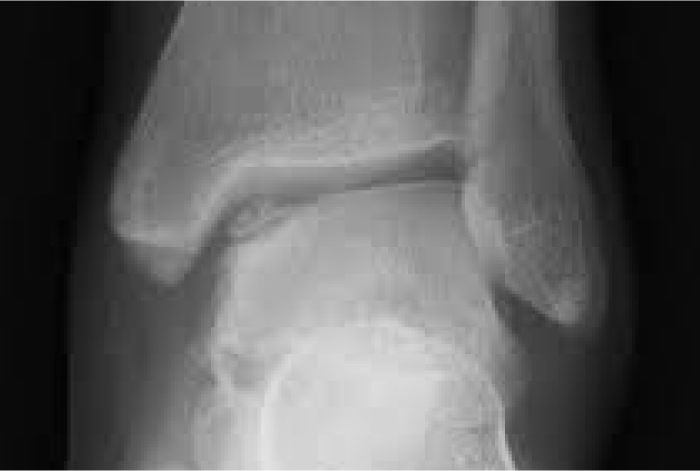

발목 관절 내 연골이 충격, 반복적 사용,

혹은 미세 손상 누적으로 인해 닳거나 떨어져 나가면서 발생하는 질환입니다.

단순 염좌로 생각하고 방치하면 연골 손상이 점차 확대되어 퇴행성 관절염으로 발전할 수 있습니다.